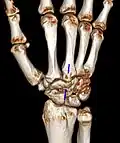

Carpal boss in der Computertomographie: VR-3D-Rekonstruktion. Pseudarthrotische Verbindung der Knochenvorsprünge am Os metacarpale 3 und am Os trapezoideum.